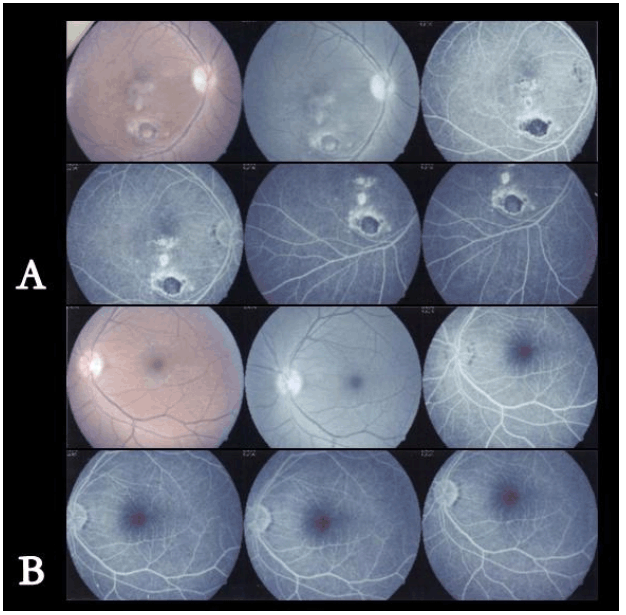

A 22-year-old male patient diagnosed with congestive cardiac failure since age of 18 years presented to emergency service with worsening of the functional class, progressive dyspnea, orthopnea and syncopal episodes. Physical examination revealed jaundice, hypotension, tachycardia, jugular venous distension, hepatojugular reflux sign, rhythmic heart sounds with a mitral murmur, rales in pulmonary bases and painful hepatomegaly. X-ray showed an enlarged cardiac silhouette and bilateral reticulonodulary opacities. Electrocardiography showed signs of dilation of the cardiac cavities. Echocardiographic findings included a severely dilated and hypokinetic left ventricle (ejection fraction less than 10%) and plurivalvular insufficiency without any structural valve damage. Cardiac catheterization confirmed these findings and showed no coronary lesions. Tests for Chaga's disease as well as other infectious and metabolic markers were negative. The patient underwent an uncomplicated cardiac transplantation after three months on waiting list, with an uneventful post-transplantation recovery. During cardiology and cardiovascular surgery follow-up he showed an excellent systolic function (ejection fraction more than 60%), but after six months he complained about gait instability that limited his walking, so he was referred to neurology consultation. After careful history taking the patient acknowledged that since age 15 he had noted a mild lower limb weakness that caused a barely perceptible disturbance in his gait pattern and that in the following years it progressed to gait instability, ataxia, dysmetria and dysarthria. These symptoms had stabilized after transplantation but subsequently worsened in the following months. Upon neurological examination important gait and stance ataxia, dysarthria, lower limb arreflexia and extensor plantar responses were found, as well as pes cavus, hammer toes and mild kyphoscoliosis. This all lead to a clinical diagnosis of FA, confirmed after genetic testing which revealed a homozygous hyper-expansion of 900 and 700 triplets in the frataxin gene. In addition he was diagnosed with Diabetes Mellitus. The patient was lost from neurology consult for the following eight years, during which his ataxia and language disturbance worsened, in spite of keeping an adequate cardiac function. He underwent nerve conduction studies and electromyography, whose results suggested a severe neuropathic pattern (Figure 1C, D). Visual evoked potentials showed disturbances of post-quiasmal visual pathway and the fluorescein angiography showed bilateral optic neuropathy and pigmentary retinopathy in the right eye (Figure 2). Cerebellar atrophy was detected by magnetic resonance imaging (MRI) scans (Figure 3).

Figure 2: Fluorescein angiography showing bilateral optic neuropathy and pigmentary retinopathy in the right eye.